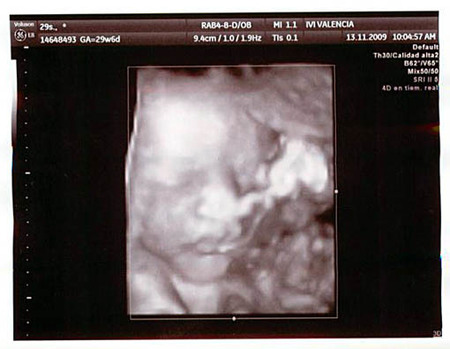

Os dejo otra imagen de Gonzalo, para que le veáis la cara:

gonzalo2.jpg